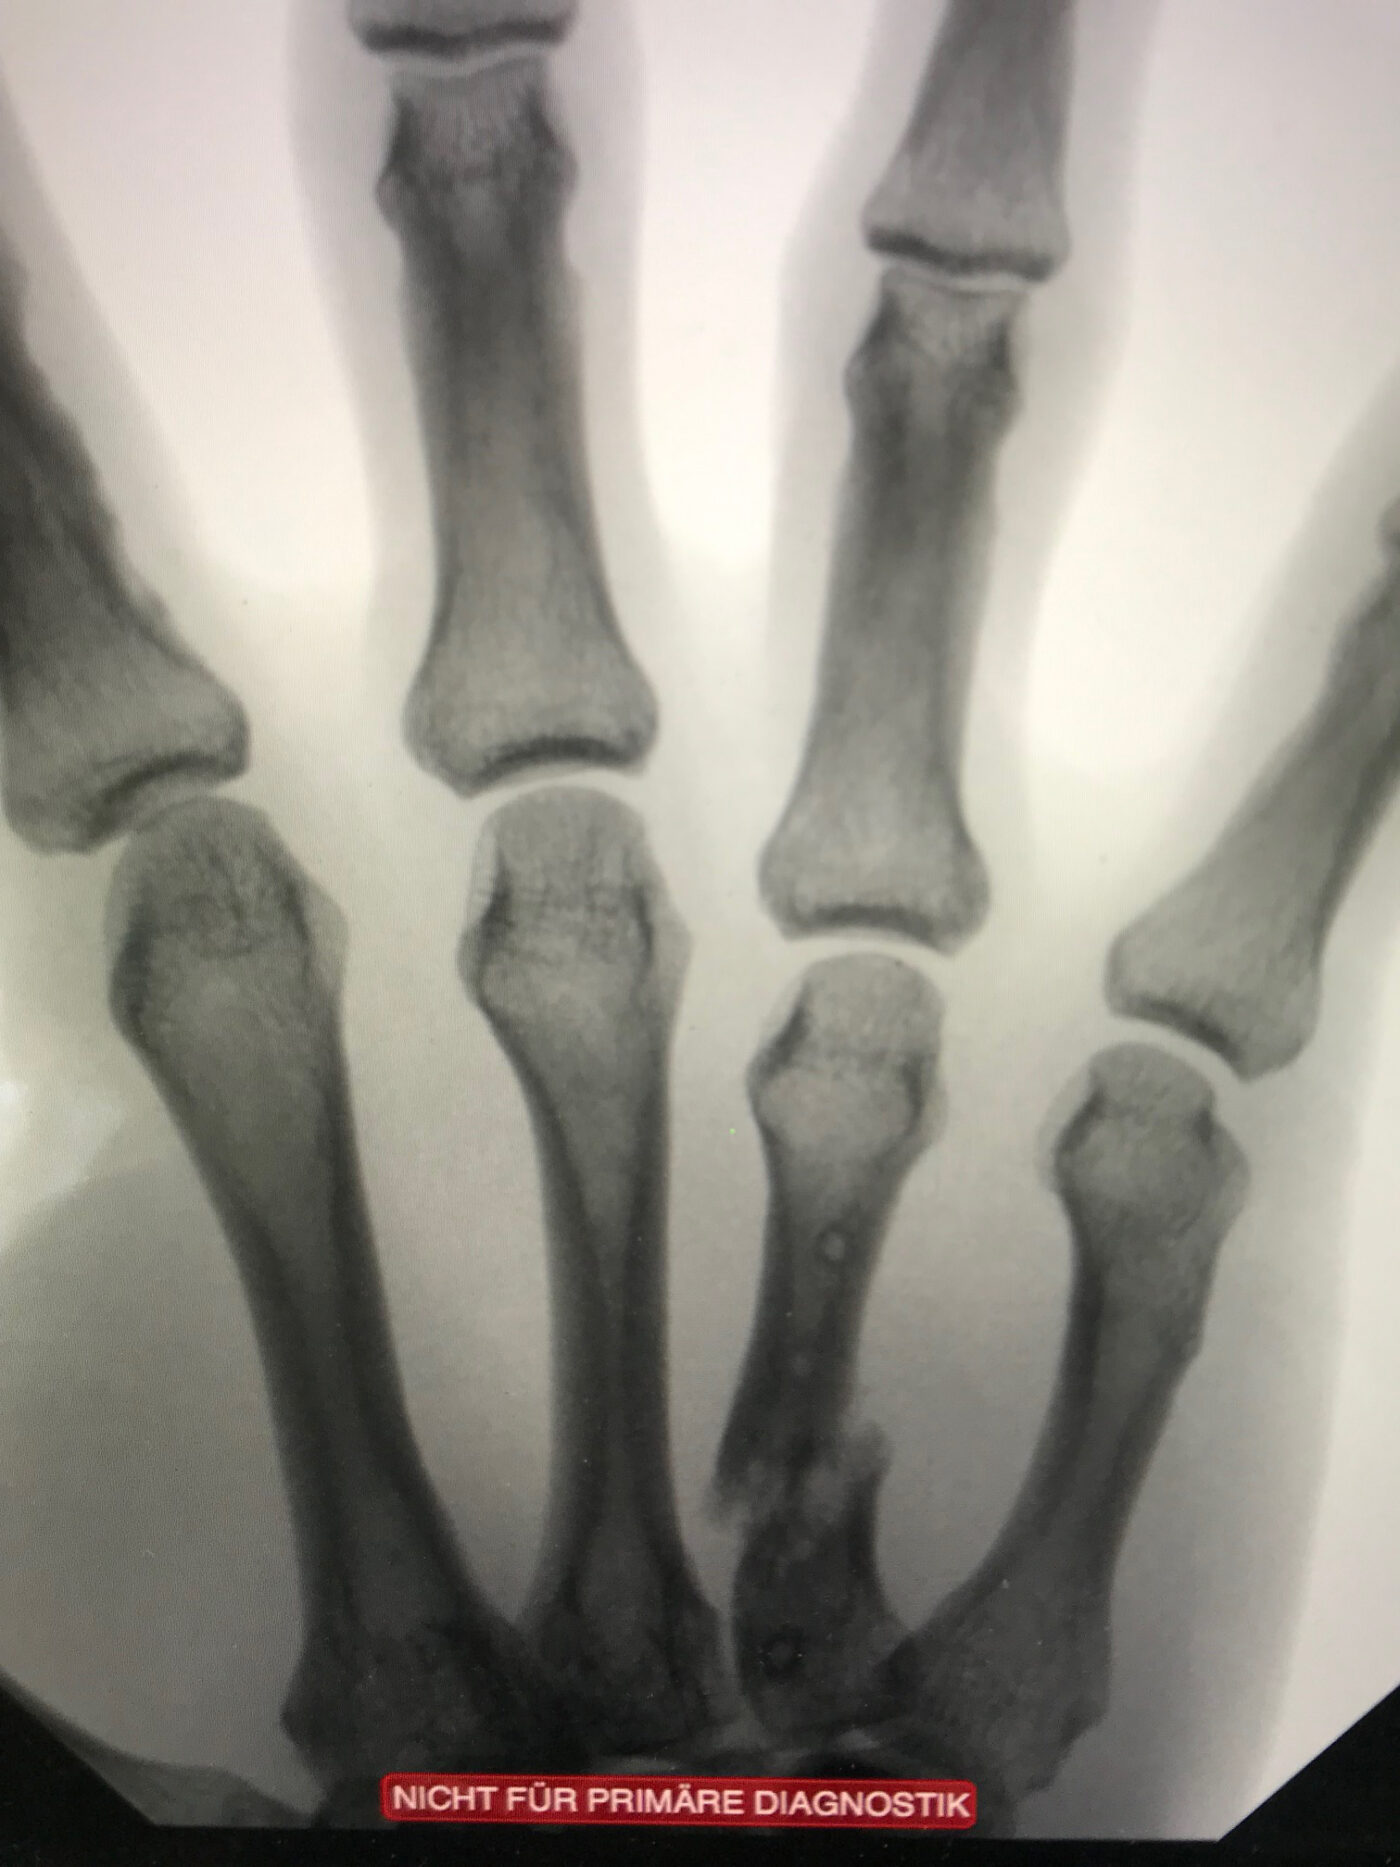

Nach Puckeinschlag mit 160 km/h: die Hand zum vierten Mal gebrochen.

Nach Knochentransplantation von der Speiche: der Mittelknochen ist repariert.

Der Kanadier erlitt zum vierten Mal einen Knochenbruch in seiner rechten Hand: Nach Zeigefinger- und kompliziertem Daumenbruch hielt ein weiterer Finger der enormen Wucht des Pucks nicht stand. «Aus ärztlicher Perspektive hätte man die Operation sofort durchführen müssen. Durch das Warten wurden die Finger immer krummer und kürzer», erinnert sich Dr. Jürgensen.

Doch solche Bedenken und Schmerzen halten Eishockeyspieler nicht vom Eis fern: Ein bisschen «Tape» muss reichen. Mit den Worten «As long as you win», liess der Handchirurg den Spieler wohl oder übel gewähren. Erst eine Woche nachdem der SCB den Sieg geholt hatte und die Siegesfeiern vorbei waren, wurde endlich operiert. In einer aufwändigen Rekonstruktion entnahm Dr. Kay Jürgensen Knochen von der Speiche und transplantierte diese an den Mittelknochen – wo vorher ein Loch war. «Den Finger habe ich wieder auf die richtige Länge gebracht und richtig eingestellt».